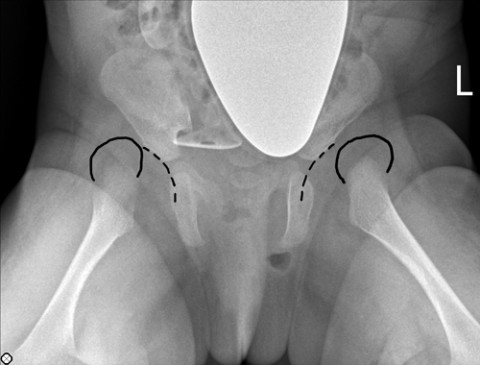

When the infant presented to us at the age of two months, both the X-ray and the ultrasound continued to showed significant dislocation of the femoral heads (Figure 1). We attempted another treatment method involving a Pavlik harness. We did, however, come to the realisation that, although the femoral heads could be brought into a better position in front of the opening to the acetabulum, there was an obstruction, which prevented the femoral head from assuming the correct position inside the acetabulum.